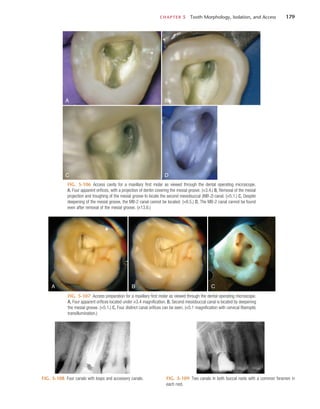

odontic explorer can be used to probe the depth of the access,

using magnification or the DOM. Often a small opening into

the chamber is present, or the dentin is very thin and the

explorer penetrates into the chamber. The depth and angle of

penetration should be assessed for any deviation away from the

long axis of the root in both the mesiodistal and buccolingual

dimensions, and the penetration angle should be realigned if